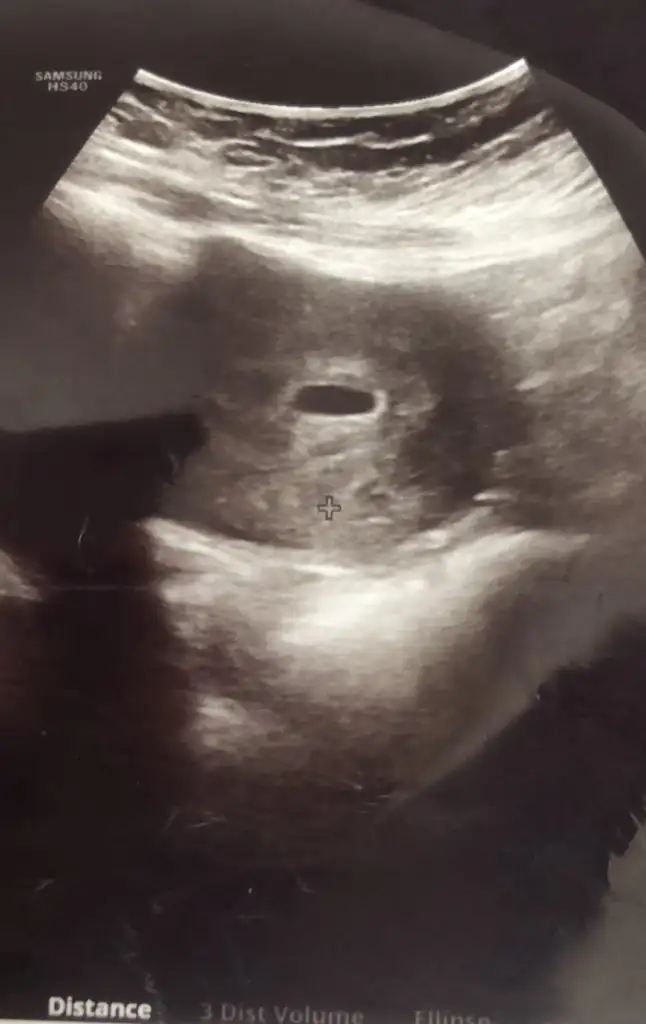

Ay ciddimisin bi yaşıma daha girdim şuna bi bakabilirmisiniz ilk çocuğumun resimleri cinsiyetini bilirse 2. Çocuğumun cinsiyetini daha erken öğrenebileceğim, çok heyecanlandım şimdidenKızlar bı arkadaş keseye göre tahmin yapıyor ve hep tutuyormuş iki oğlunu da bu şekilde cok yeniyken bile tahmin etmiş...ogullarinda kesesi hep uzunmuş muz gibi...yuvarlak ve yuvarlağa yakın olanlar hep kızdır diyor..ve bayağı emin konusuyor..benimki şişman bı fasulye gibi oo kesin kız görürsün dedi...sizlerin keselerinin şekli nasıldı ve cinsiyet neydi konusalimmi

Kesenin ucu mu yuvarlak ya da uzun olacak. 5 haftalık benim bebeğim kesenin ucunda muz gibi bir uzantı varKızlar bı arkadaş keseye göre tahmin yapıyor ve hep tutuyormuş iki oğlunu da bu şekilde cok yeniyken bile tahmin etmiş...ogullarinda kesesi hep uzunmuş muz gibi...yuvarlak ve yuvarlağa yakın olanlar hep kızdır diyor..ve bayağı emin konusuyor..benimki şişman bı fasulye gibi oo kesin kız görürsün dedi...sizlerin keselerinin şekli nasıldı ve cinsiyet neydi konusalimmi